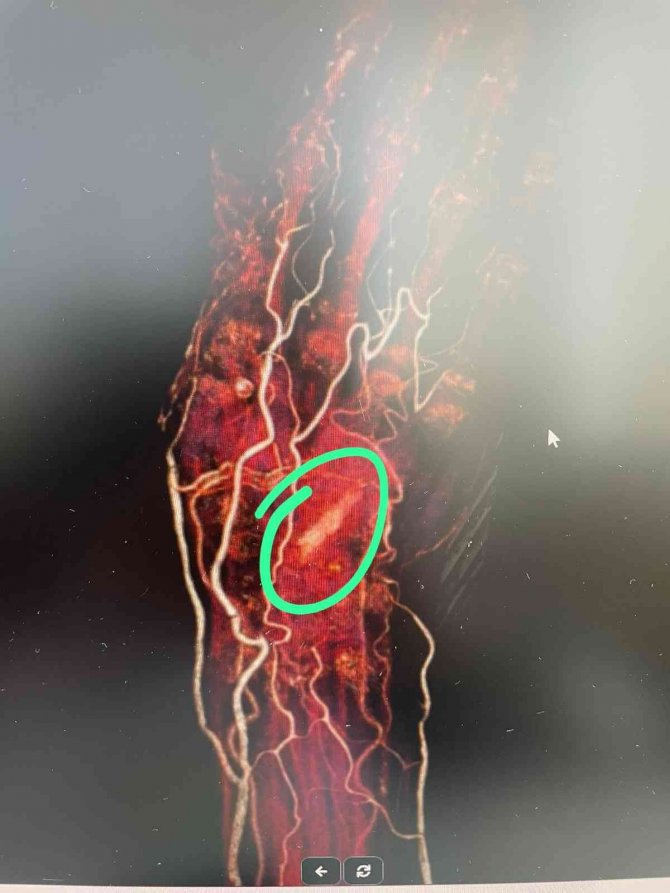

Her geçen gün elinin acısının şiddetini arttırdığını ve elinin hem ön hem de arka tarafından derisinin delinerek akıntı olmaya başladığını belirten Raziye Baş, "Kalça kırığı çok acı veren bir durum olmasına rağmen elimin acısından durmaz hale geldim. Tekrar hastaneye geldim. Günlerce hastanede yattım. Kolumdan film ve MR çekilmesine rağmen kimse bu film ve MR'a bakmadı. Enfeksiyon geçer diye tam 7 ay beklettiler. Kolumu kullanamaz ve yalnız başıma hayatımı sürdüremez hale geldim. Bir yakınımın tavsiyesi ile bu defa İzmir'e başka bir hekime gittim. Doktor beraberimde götürdüğüm film ve MR'ı bakar bakmaz içeride bir cisim olduğunu belirtip hemen ameliyata aldı. Elimin içinden büyük bir odun parçası çıkarıldı. Kısa sürede sağlığıma kavuştum" diyerek kendisini aylardır acı çektiren kişi ve kişilerden şikayetçi olduğunu söyledi.

İlk gittiği hastanede çekilen film ve MR'ı da paylaşarak yaşadığı acının sıradan bir sağlık sorunu değil tamamen ihmalden kaynaklandığını ileri süren Raziye Baş, "Ben "canım çok yanıyor elimi hareket ettiremiyorum" dedikçe Aydın'daki doktor beni tembellikle suçladı. "Tembel olduğun için elini hareket ettirmiyorsun" deyip benim psikolojimi de bozdular. İnsan önündeki film ve MR'a bakmaz mı? Bana 7 ay boyunca adeta işkence ettiler" diyerek yaşadıklarına isyan etti.